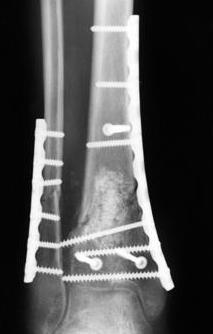

3.	стабилизировать наружный опорный комплекс голени и предотвратить

вальгусную деформацию голеностопного сустава. Конечно, данная проблема

не очень актуальна, или вовсе не актуальна для 43С1, но для повреждений

типа 43С2,3, особенно в случаях, когда метафизарный дефект потребовал

пластики, а пластину пришлось уложить по медиальной стороне --

остеосинтез малоберцовой кости является крайне необходимым -- привожу

характерный пример. Но, перелом малоберцовой кости может быть и много